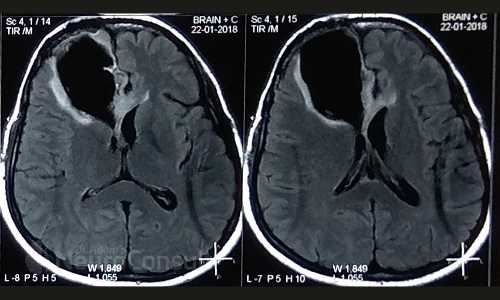

My Cases Studies & Work